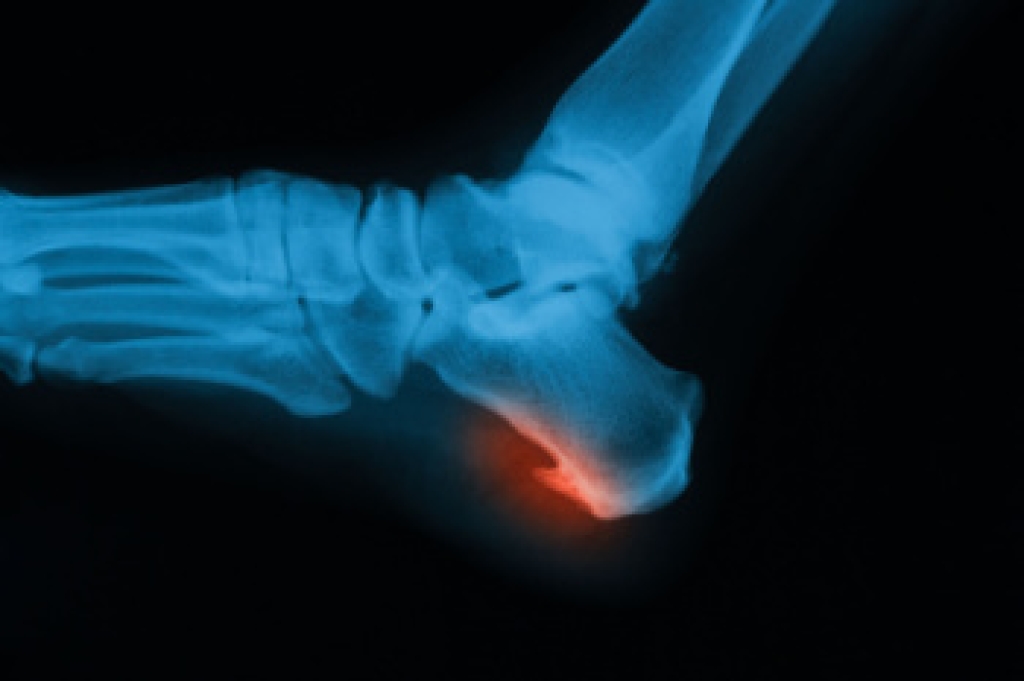

Foot pain caused by arthritis can be debilitating, affecting mobility and quality of life. Arthritis in the feet often presents with symptoms such as joint stiffness, swelling, tenderness, and reduced range of motion. This pain may worsen with activity and improve with rest, making it challenging to engage in daily tasks comfortably. Different types of arthritis can affect the feet, including osteoarthritis, rheumatoid arthritis, and gout. Osteoarthritis typically develops due to wear and tear on the joints over time, while rheumatoid arthritis is an autoimmune condition that affects the lining of the joints. Gout results from the accumulation of uric acid crystals in the joints. If you have foot pain that persists or worsens, especially if accompanied by other symptoms like swelling or warmth in the joints, it is suggested that you schedule an appointment with a podiatrist for an accurate diagnosis and treatment. If the pain is determined to be arthritic, a podiatrist can offer relief methods to help maintain mobility and enhance your quality of life.

Arthritis is a joint disorder that involves the inflammation of different joints in your body, such as those in your feet. Arthritis is often caused by a degenerative joint disease and causes mild to severe pain in all affected areas. In addition to this, swelling and stiffness in the affected joints can also be a common symptom of arthritis.